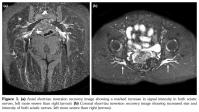

A 52-year-old female patient was referred to the clinic with complaints of bilateral buttock and leg pain for the last one year. In the initial interview, the patient complained of bilateral buttock pain radiating to both legs without improvement despite the use of nonsteroidal anti-inflammatory drugs and physical therapy. Her complaints started after a traumatic injury. Upon detailed questioning, she mentioned she had fallen on her buttocks severely after adjusting the treadmill to a high speed and altering the treadmill’s incline settings during her first use. The patient’s medical history was not notable except for a cholecystectomy three years earlier. On physical examination, there was a full active range of motion of all the lower limb joints and the lower back. Bilateral hip movements were painful with bilateral hip flexion and internal rotation. The straight leg raise test was positive on the left and right at 60 and 50 degrees, respectively. Her neurological and neurovascular examinations were normal. In addition, complete blood count, routine blood biochemistry, and acute phase reactants were within normal range. Bilateral piriformis syndrome was suspected after exclusion of the other pathologies using electrodiagnostic studies and lumbar magnetic resonance imaging. Her physical examination was repeated. She had tenderness to external palpation over greater sciatic notches on both sides. Flexion+adduction+internal rotation, Beatty, and Pace tests were positive bilaterally. Pelvis magnetic resonance imaging documented that both sciatic nerves were increased in intensity in the axial and coronal short-tau inversion recovery sequences (Figure 1a and b). After obtaining informed consent, the patient was administered an ultrasound-guided injection of 4 mL lidocaine 2% and 1 mL betamethasone dipropionate into both piriformis muscles using a 22G 88-mm spinal needle.(1) After the procedure, her pain decreased substantially (pre- and post-treatment visual analog scale scores for pain were 8 and 4, respectively). In the light of these findings, the patient was diagnosed with bilateral piriformis syndrome. Further treatments, including the spray and stretch technique, were incorporated two times as the pain was maintained at a visual analog scale level of 4/10.(2) At the six-week follow-up, she was completely asymptomatic. On physical examination, piriformis-specific tests were also negative for both sides.

Piriformis syndrome is an entrapment neuropathy of the sciatic nerve at the level of the piriformis muscle.(3) An ultrasound-guided injection of local anesthetics and steroids into the piriformis muscle may contribute to both diagnostic and therapeutic aims.(1) In this case, based on the abnormal findings from the magnetic resonance imaging, a corticosteroid-anesthetic mixture was injected into the piriformis muscles. The relief of the symptoms following the injection confirmed the diagnosis and provided an effective treatment. It is assumed that the resolution of the patient’s complaints after the injection might be the result of the anti-inflammatory action of the steroid.